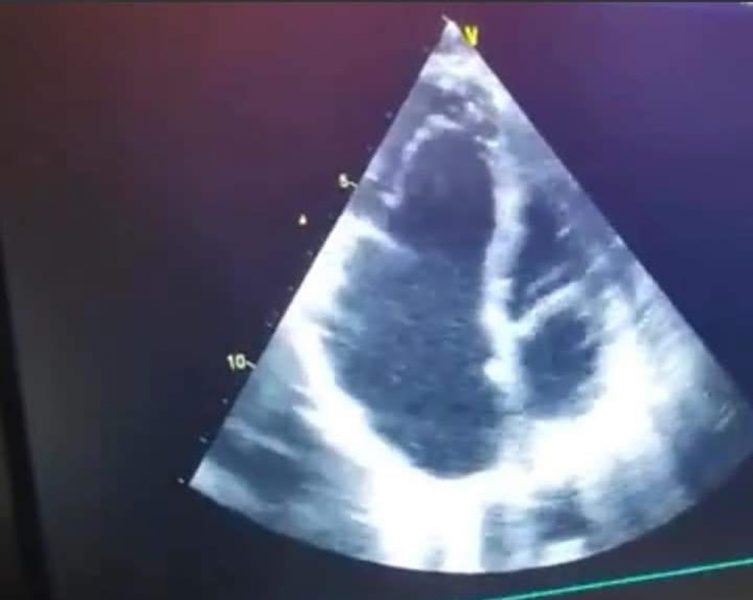

-Eдна од повеќето причинители на трикуспидна инсуфициенција со регургитација на крв од десна комора во десна преткомора покрај реуматската треска, тапи трауми во граден кош, ендокардити е и Eбштајновата аномалија – Ebsteins anomaly или деснострана атријализација на срцето при што трикуспидните кусписи се изместени вродено апикално кон коморите при што десната преткомора е поголема од вообичаено на ехокардиографија исто постои и подолги залистоци нивно треперење и даден степен на трикуспидна инсуфициенција.

При ебштајновата аномалија често има и други вродени дефекти како вентрикуларен септален дефект, атријален септален дефект, коарктрација на аорта итн.